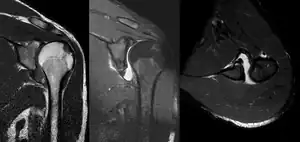

MRI of shoulder after dislocation with Hill-Sachs lesion and labral Bankart's lesion.

In young adults engaged in highly demanding activities shoulder surgery may be considered.[20] Arthroscopic surgery techniques may be used to repair the glenoidal labrum, capsular ligaments, biceps long head anchor or SLAP lesion or to tighten the shoulder capsule.[21]

Arthroscopic stabilization surgery has evolved from the Bankart repair, a time-honored surgical treatment for recurrent anterior instability of the shoulder.[22] However, the failure rate following Bankart repair has been shown to increase markedly in people with significant bone loss from the glenoid (socket).[23] In such cases, improved results have been reported with some form of bone augmentation of the glenoid such as the Latarjet operation.[24][25][26]